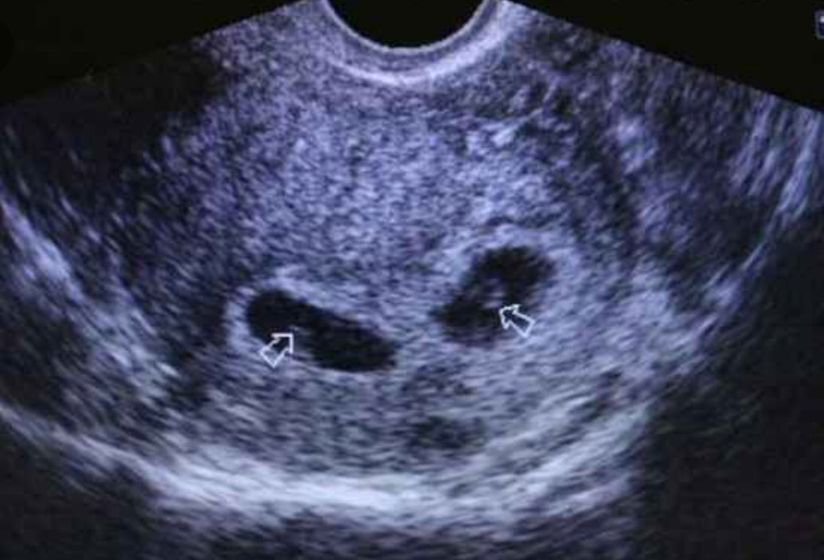

УЗИ мне делали примерно 5-6 нед, может вам к другому узисту сходить? А УЗИ на фото ваше?

Нееее, это взяла я фото просто для темы. У меня на 2,5 недели только одно плодное увидели, а жёлтых тела 2